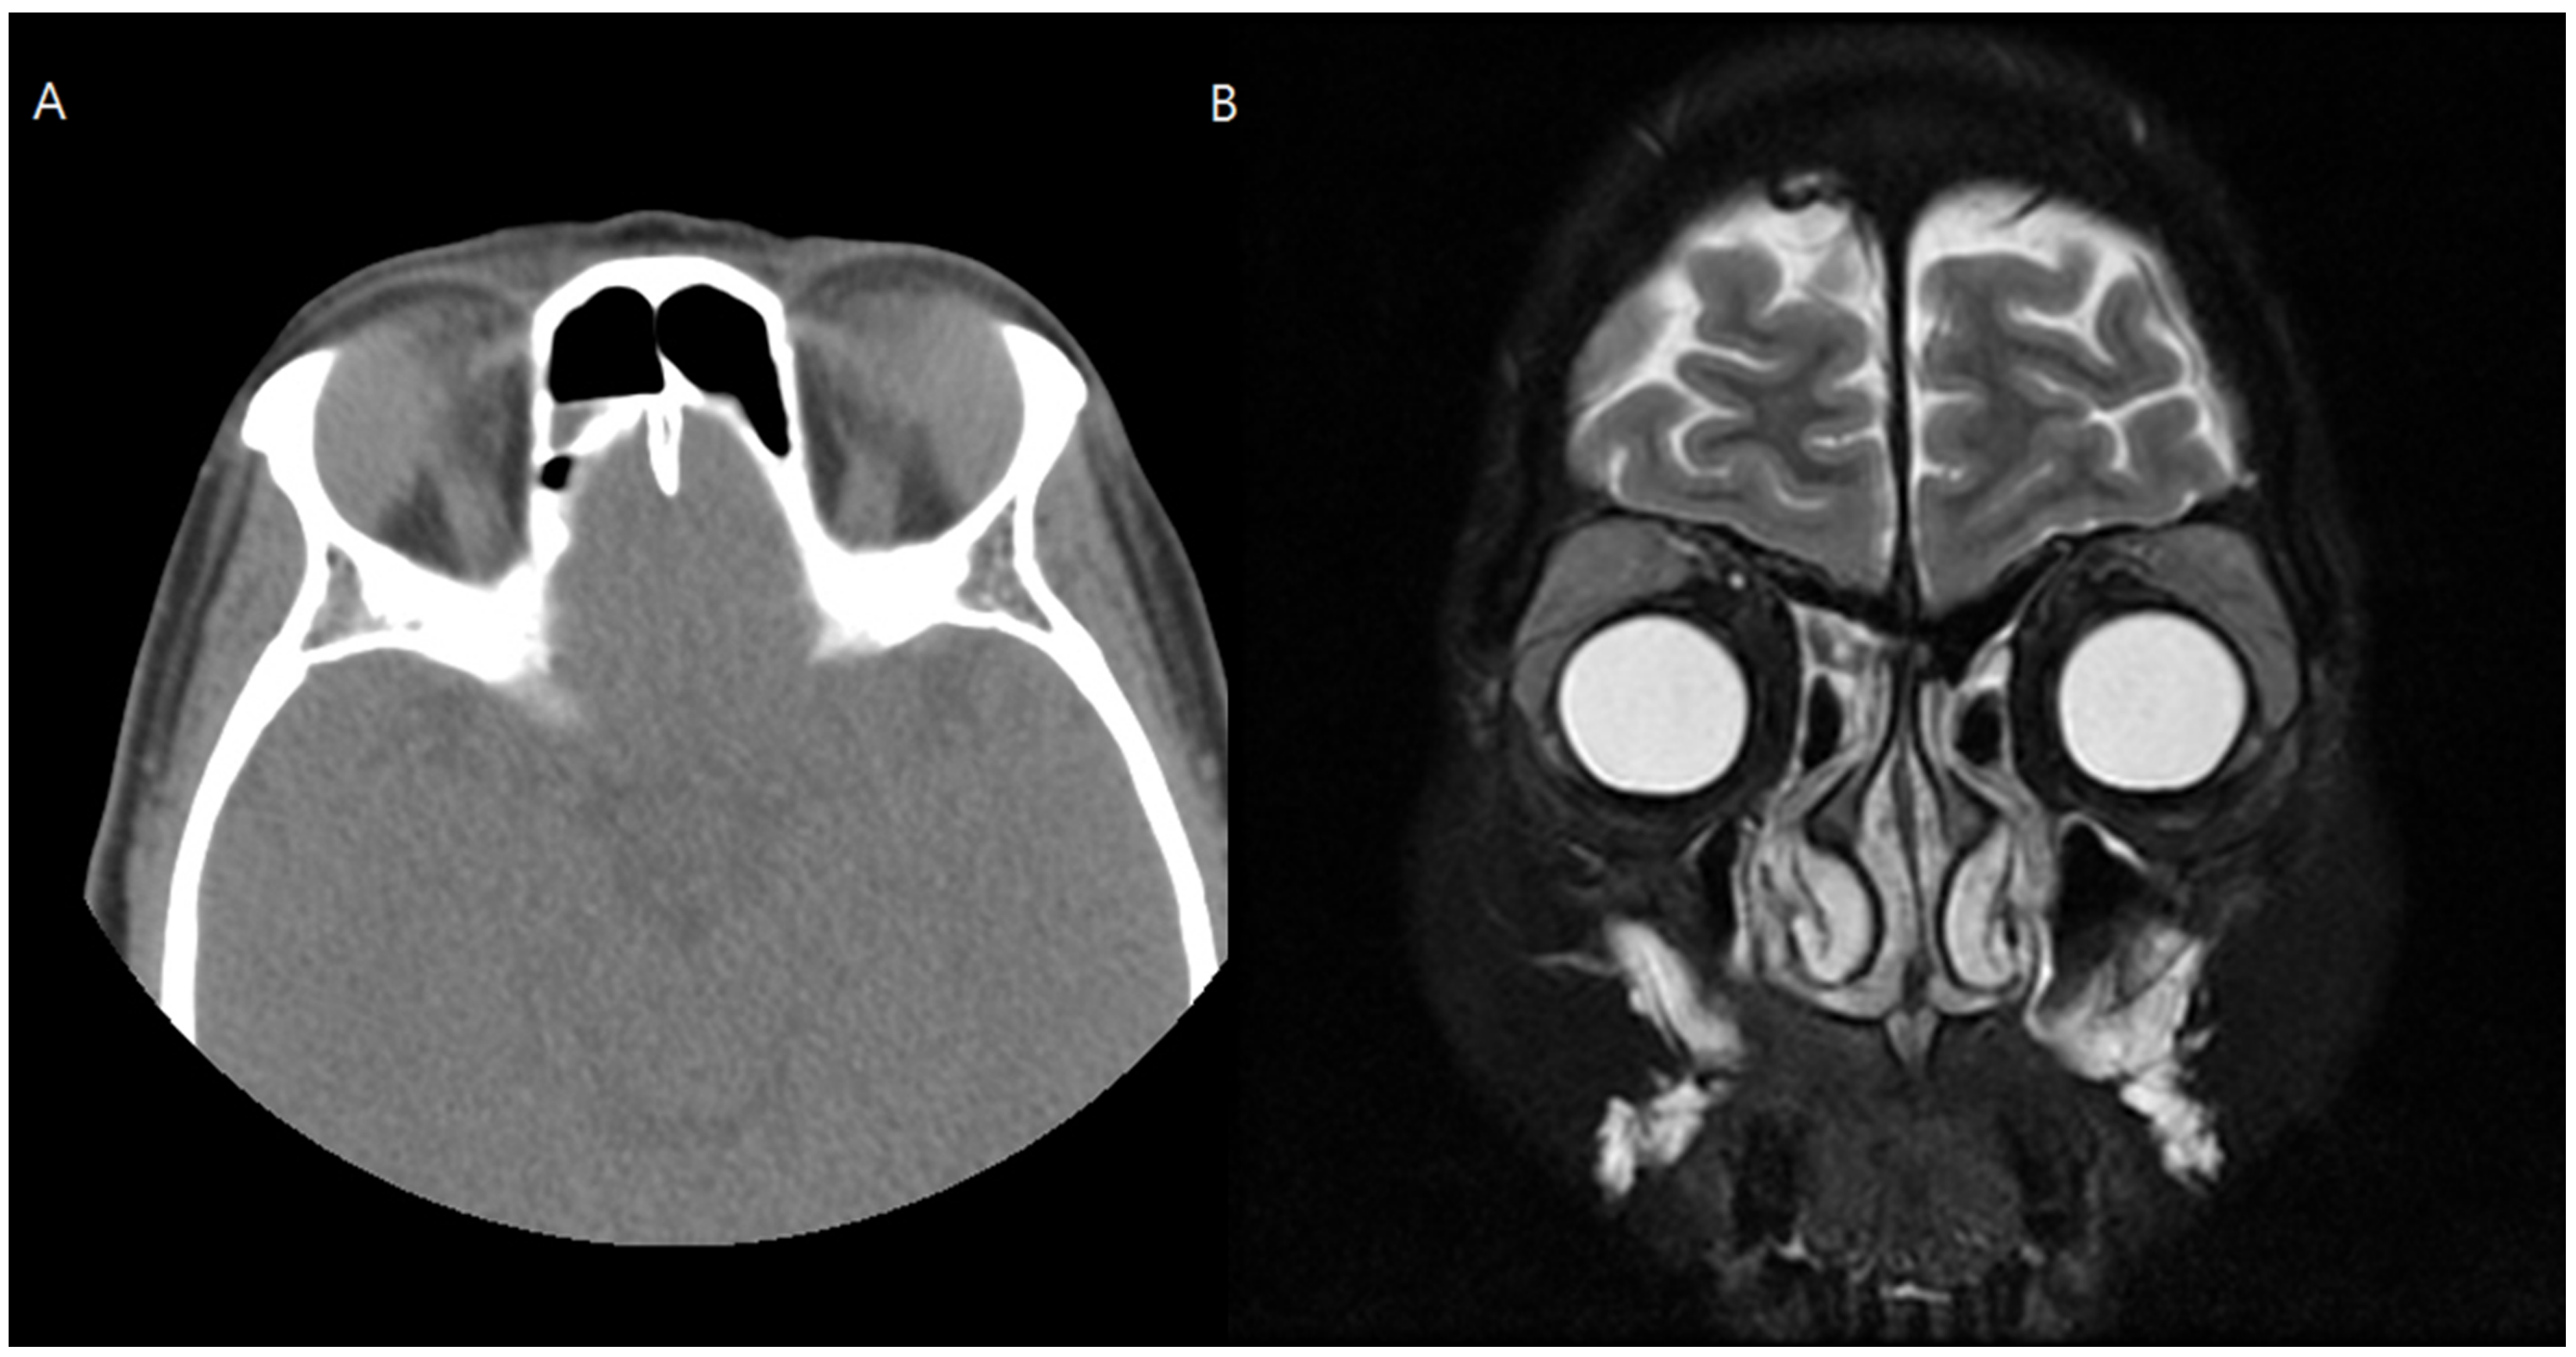

A 52-year-old female patient with a chief complaint of swelling in both upper eyelids accompanied by diplopia visited our medical center. In orbital CT and magnetic resonance imaging scans, bilateral lacrimal gland hypertrophy was observed (Figure 3). Incisional biopsy of the bilateral lacrimal gland was performed to differentiate a diagnosis of lacrimal gland lymphoma from that of immunoglobulin G4 (IgG4)-related ophthalmic disease. The lacrimal gland tumor was approached via transconjunctival incision, and a biopsy was performed. Lacrimal gland biopsy with immunohistochemical staining of IgG4 showed a number of benign cells. Her blood test results showed increased IgG4 levels, and IgG4-related lacrimal adenitis was confirmed.

Figure 3. Preoperative computed tomography (A) and magnetic resonance imaging (B) of Case 2. Enlarged lacrimal glands were noted in both orbits.